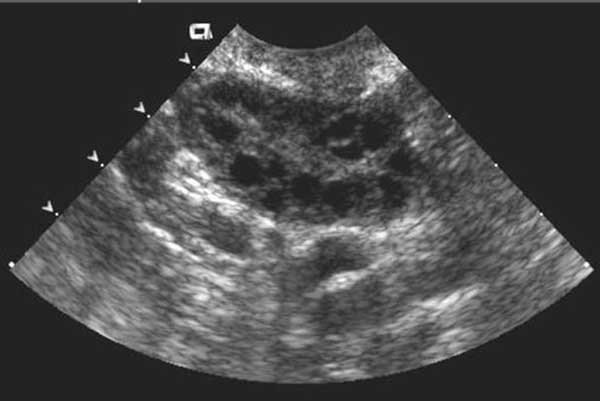

Follicle Study Ultrasound Images

Follicle study ultrasound images help to study the condition of the follicles, uterus, and uterine lining. With the help of a transvaginal follicular scan, the doctors can see the ruptured follicles and also the ones with matured eggs.

This process takes a few minutes and will help sort out any problems related to the ovaries. Women who suffer from PCOS need this scan to see if the medicine they use is helping the follicles or not.

MSF in a follicular study is quite common. It might occur in the right or left side of the uterus. However, MSF means multiple small follicles, also known as antral follicle count. By the follicular study, the doctor can study these small follicles and see if they can produce any mature egg for ovulation or not. Also, if they cause problems in the ovary, the doctor can start the necessary treatments.